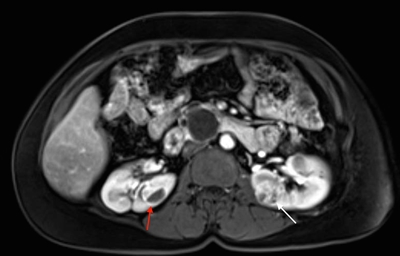

Hemangioblastomas are the most common disease manifestation in patients with VHL, affecting more than 70% of individuals. A prospective study assessed the natural history of hemangioblastomas.[16] The mean age at onset of central nervous system (CNS) hemangioblastomas is 29.1 years (range, 7–73 y).[17] CNS hemangioblastomas were most commonly seen in the cerebellum (45%), spinal cord (36%), cauda equina (11%), and brain stem (7%).[18] While sporadic hemangioblastomas are generally solitary in nature, the VHL-associated CNS lesions are often multifocal. After a mean follow-up of 7 years, 72% of the 225 patients studied developed new lesions.[18] Figures 2 and 3 depict cerebellar and spinal hemangioblastomas, respectively, in patients with VHL.

Sagittal view of an individual's neck showing several light-colored lesions along the spinal cord.

Figure 3. Hemangioblastomas are the most common disease manifestation in patients with von Hippel-Lindau disease. Multiple spinal cord hemangioblastomas are shown.